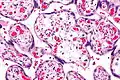

| Micrograph of villous immaturity. H&E stain. | |

Placental villous immaturity is chorionic villous development that is inappropriate for the gestational age.

Immature chorionic villi are larger and have more central blood vessels; thus, the diffusion distance for gas and nutrient exchange is larger and, therefore, placental function is impaired.

Low mag.

Low mag. High mag.